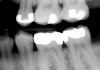

A patient presented for treatment with clinical and radiographic evidence of caries on the distal surface of the mandibular second premolar (Figure 1). The adjacent mandibular first molar had a defective amalgam restoration that was scheduled to be replaced with a core and prepared for a full crown at a future appointment. After administration of local anesthesia, a dental dam was placed. A sycamore wedge was firmly placed into the distal gingival interproximal embrasure before starting the preparation to achieve rapid separation of the tooth from its adjacent tooth to compensate for thickness of the thin, metal matrix (Figure 2). The tooth was prepared with a 245 bur with a high-speed handpiece and water spray. When restoring the proximal contact with composite resin, this author prefers to use a thin, dead-soft, stainless-steel matrix band that allows for shaping and achieving a positive, anatomic proximal contact. For this case the decision was made to use a silicone-covered split-tine ring with a sectional, thin, dead-soft, stainless-steel matrix. The silicone-coated ring is stable on the tooth and continues to apply pressure during restoration placement to ensure an anatomic proximal contact, while its shape allows for placement without interference from the gingival wedge. Also, the matrix has a tab extension that makes it easy to hold and place using a special forceps (Figure 3). Once the band was placed, an anatomic, flexible, polymeric wedge was placed using the same forceps.

Figure 1a  Mandibular second molar with distal caries. Clinical view.

Figure 1a

Figure 1b  Mandibular second molar with distal caries. Radiographic view.

Figure 1b